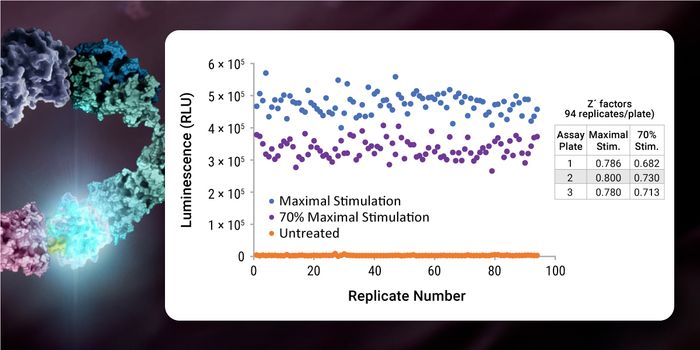

NOV 07, 2023ImmunologyPublished by Beata Boczkowska, Ph.D. Interleukin-18 (IL-18) is an effective pro-inflammatory cytokine for the host defen ...